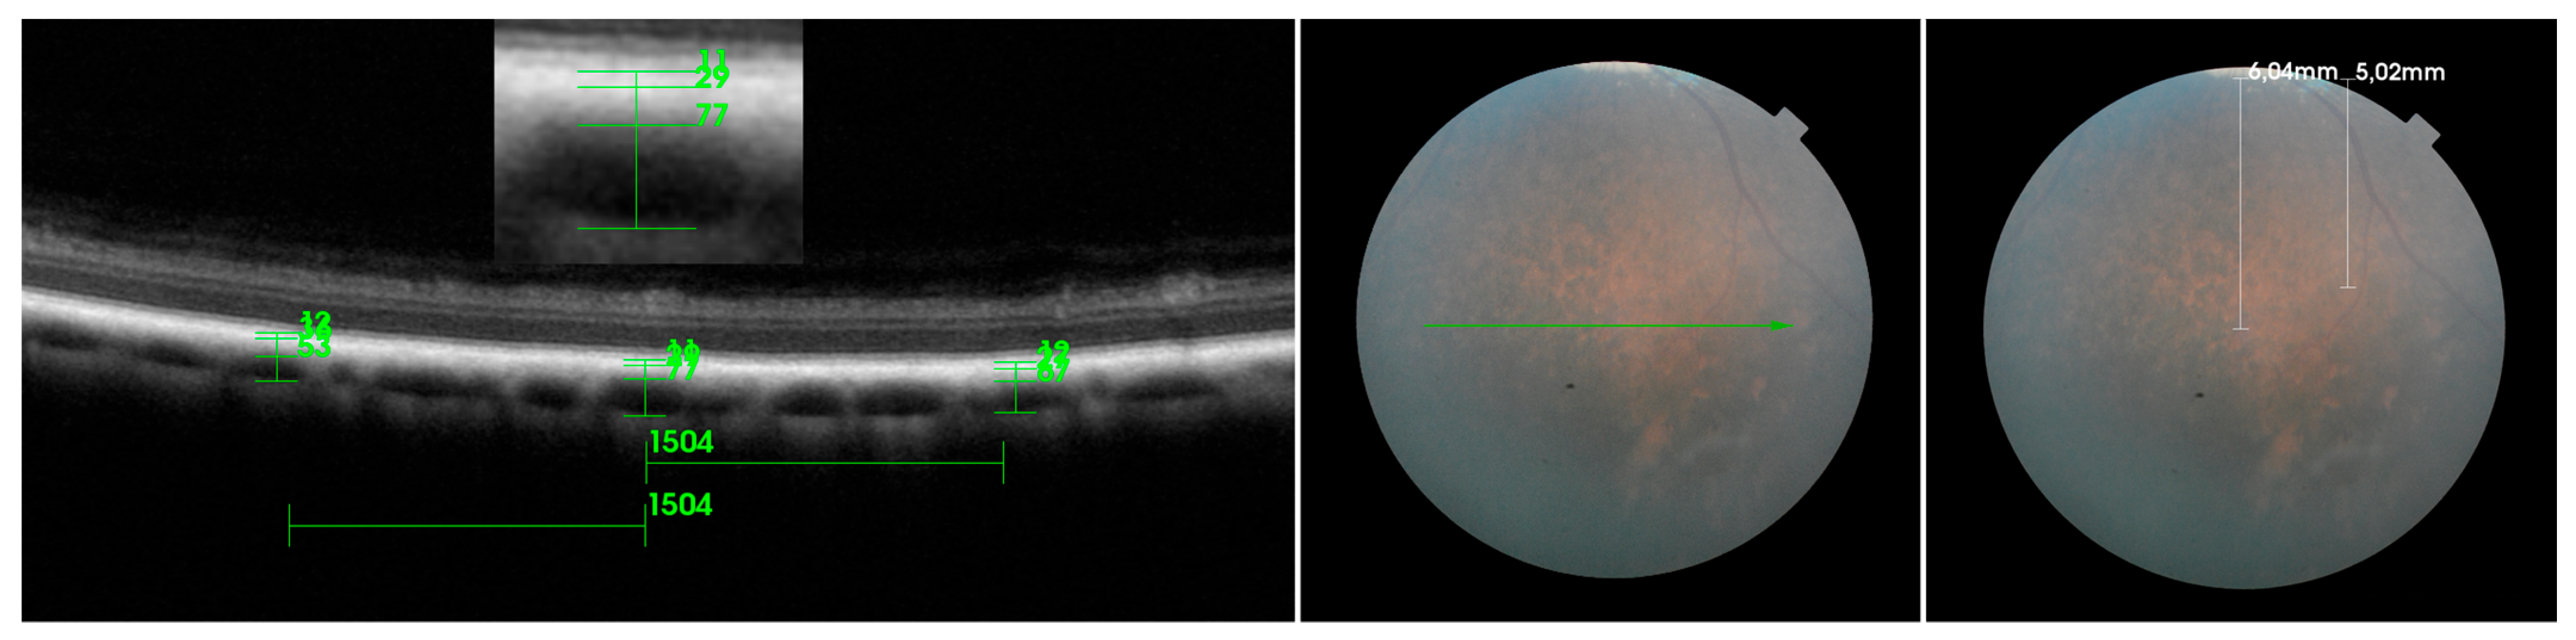

3. Results